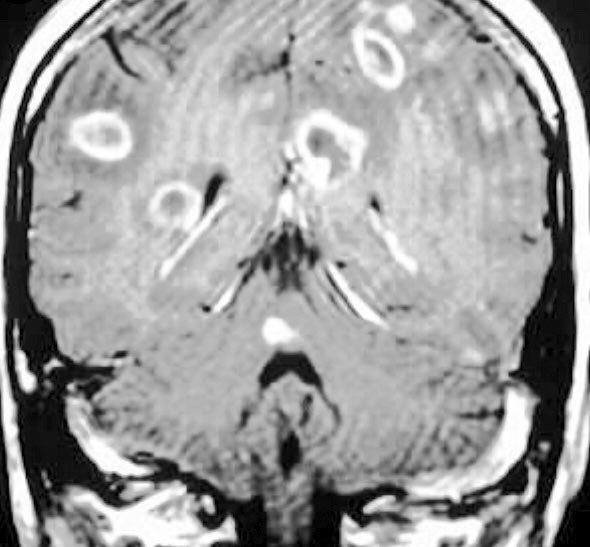

Which are the pathologies related with ring enhancing lesions in a contrast ct. The differential for peripheral or ring enhancing cerebral lesions includes. A ring enhancing lesion is an abnormal radiologic sign on mri or ct scans obtained using radiocontraston the image there is an area of decreased density see radiodensity surrounded by a bright rim from concentration of the enhancing contrast dyethis enhancement may represent breakdown of the blood brain barrier and the development of an inflammatory capsule.

Magic dr or dr magic dr magic l magical dr mnemonics magic dr or dr magic m. March 27 2014 ivan gonzalez a favorite of the usmle steps nbme internal medicine shelf and abim internal medicine board exams seems to be those ring shaped lesions picked up on imaging studies. M1mc1450 a 41 year old male with a history of pneumocystis jiroveci pneumonia is found to have multiple ring enhancing lesions on brain ct.

Infarct subacute phase inflammatory ne. I think its d. Often the scenario is a ring lesion identified on a ct head scan in an immunocompromised patient particularly one with hiv or aids.

Usmle step 1 is the first national board exam all united states medical students must take before graduating medical school. Cerebral abscess tuberculoma neurocysticercosis metastasis glioblastoma subacute infarcthemorrhagecontusion demyelination incomplete ring tumefactive demyeli. Thank you for your replies.